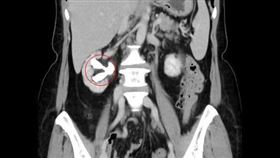

罕見!醫驚見「3顆睪丸伯」:90歲還掛外面

男性睪丸主要作用為產生精子及分泌雄性激素睪固酮,一般...